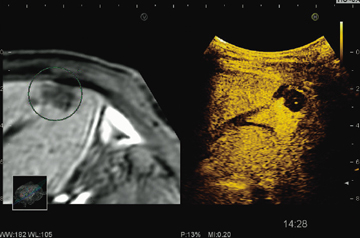

また,組織成分からの反射エコーを抑制し,造影剤からの反射エコーを高感度にて選択的にカラーマッピング表示する,Color Wideband Pulse Inversion機能も搭載した。これらの機能は,超音波画像と同一断面のCT/MR/USのスライス断面をリアルタイムに並列表示するReal-time Virtual Sonography(RVS)と併用可能である(図3)。